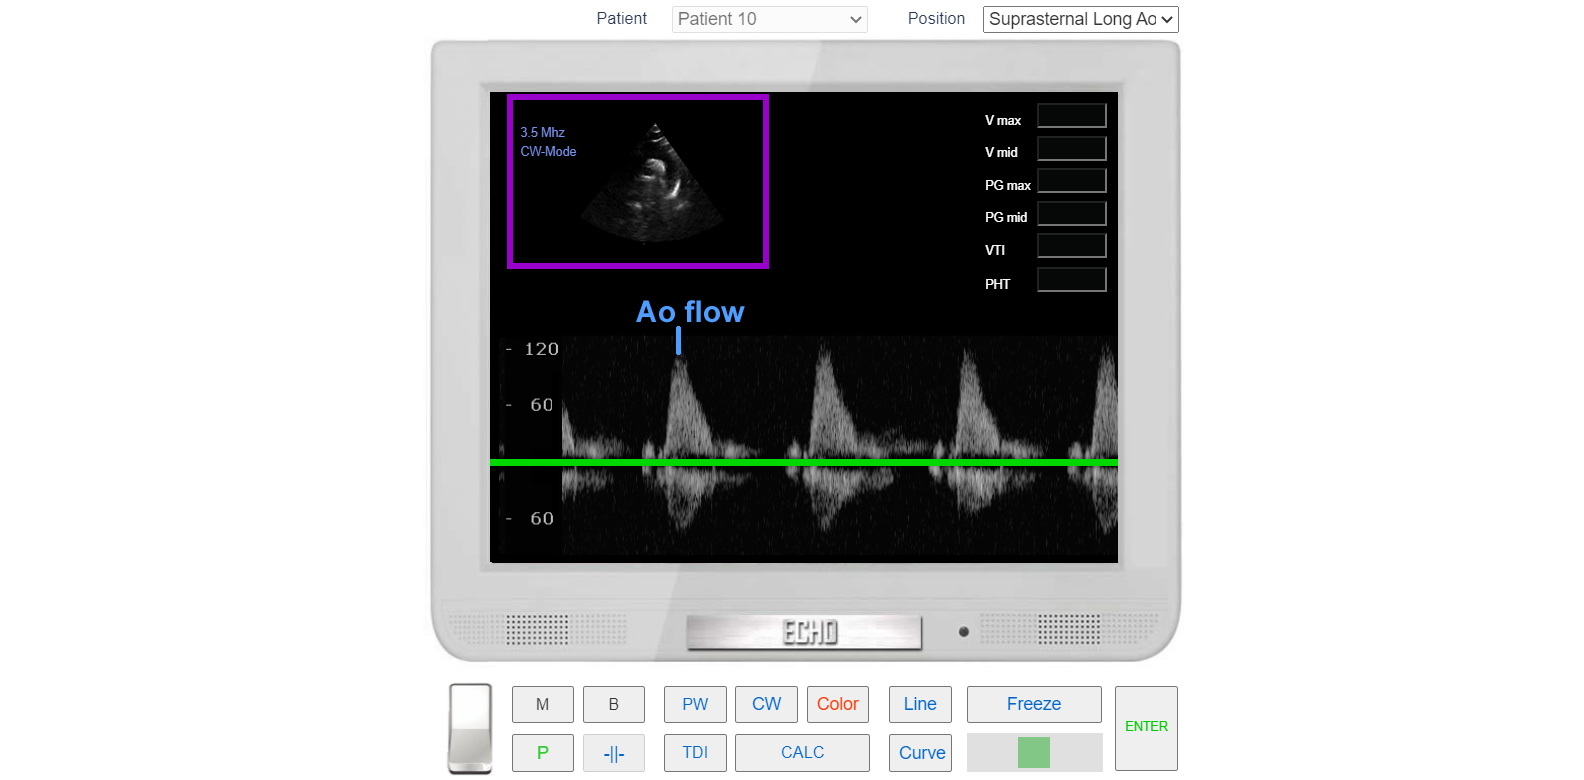

In the case of the Suprasternal Approach, The flow is directed towards the transducer and located above the baseline.

Suprasternal view Long axis. Asvending Aortic flow. CW Doppler